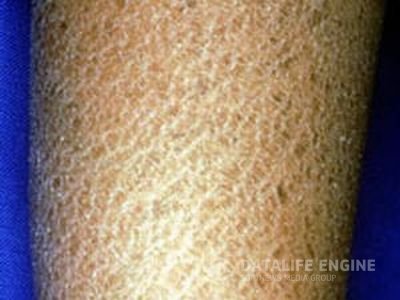

Ихтиоз («рыбья чешуя»)При ихтиозе кожа становится очень сухой и шелушится, что дало повод назвать это заболевание «рыбьей чешуей».... Ихтиоз («рыбья чешуя»)При ихтиозе кожа становится очень сухой и шелушится, что дало повод назвать это заболевание «рыбьей чешуей»....